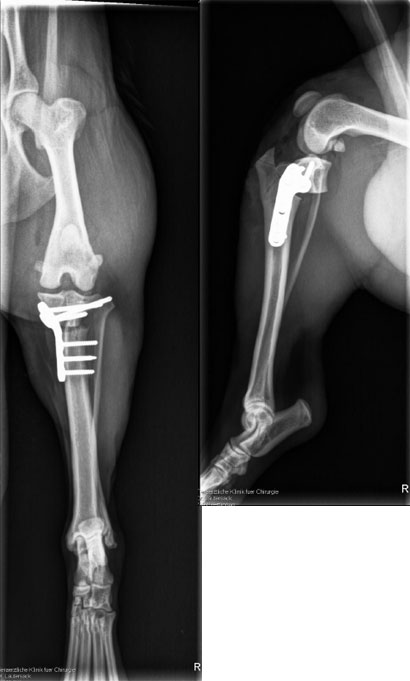

Der arme Justin hat zwar eine lockere Kniescheibe sowie einen Kreuzbandriss diagnostiziert bekommen aber das heißt auch - und das ist sehr wichtig - er wird wieder gesund werden und normal weiterleben ohne Einschränkungen!

++klick für gross++